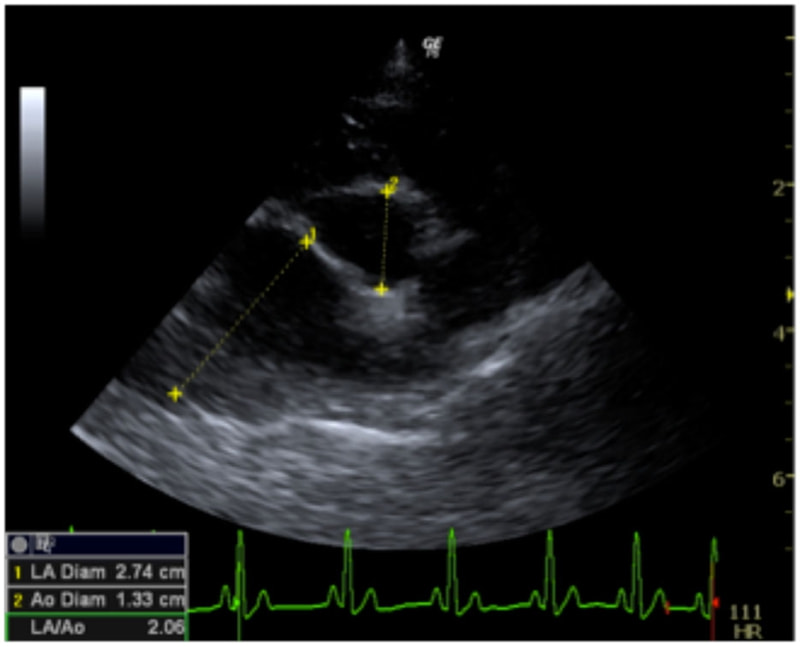

症例6:【ACVIM StageD ビーグル 10歳 去勢雄】

D:La/Ao比の重度拡大あり

左側胸壁心尖部領域を最強点とするLevine 5/6の収縮期性心雑音が聴取された。安静時にも咳が認められる。胸部レントゲン検査において重度の心拡大が及び肺水腫が認められた。超音波検査では、重度の僧帽弁閉鎖不全、三尖弁閉鎖不全が認められた。三尖弁逆流速度から肺高血圧症が示唆された。ACE阻害薬、ピモベンダン、硝酸イソソルビド徐放剤、ベラプロストナトリウム、利尿剤としてフロセミド及びスピロノラクトンを用いて治療を行っている。